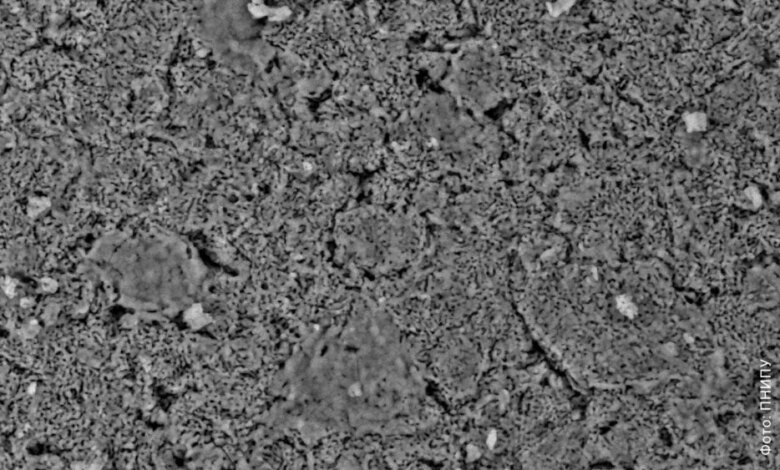

تبلغ مساحة سطحه الداخلي 266 مترًا مربعًا لكل جرام – مما يعني أنك إذا قمت بتوسيع جميع جدران المسام الداخلية عقليًا بجرام واحد فقط من هذا المسحوق، فإنها ستغطي مساحة تعادل ملعب تنس. في الوقت نفسه، تكون المادة “فسيحة” للغاية: يصل حجم مسامها إلى 0.34 سم مكعب لكل جرام، والمسام نفسها صغيرة بشكل لا يصدق – يبلغ نصف قطرها 2.6 نانومتر فقط.

هذا المزيج من مساحة ضخمة، وحجم كبيريكونma والمسام الصغيرة جدًا تفتح تطبيقين مهمين في الطب.